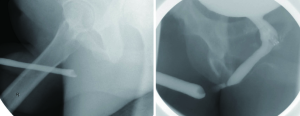

The presence of a urethral distraction after PFUI presents a unique utilization of cystoscopy. In these cases, cystoscopy is frequently required to accurately assess the length of a stricture. These patients often have a completely obliterated segment, and are unable to sufficiently relax the bladder neck during voiding studies to visualize the posterior urethra. As such, in conjunction with retrograde urethrogram, contrast-based assessment alone can result in significant overestimation of the length of the distraction defect. In these instances, antegrade cystoscopy can be performed through the suprapubic tract, and the cystoscope can be advanced through the bladder neck to the level of the stricture. In combination with RUG, this maneuver can assist in accurate identification of distraction length (Figure 8). Correct identification of distraction length can be useful in planning surgical intervention to restore urethral patency, and can assist in predicting outcomes during the reconstruction of these defects.